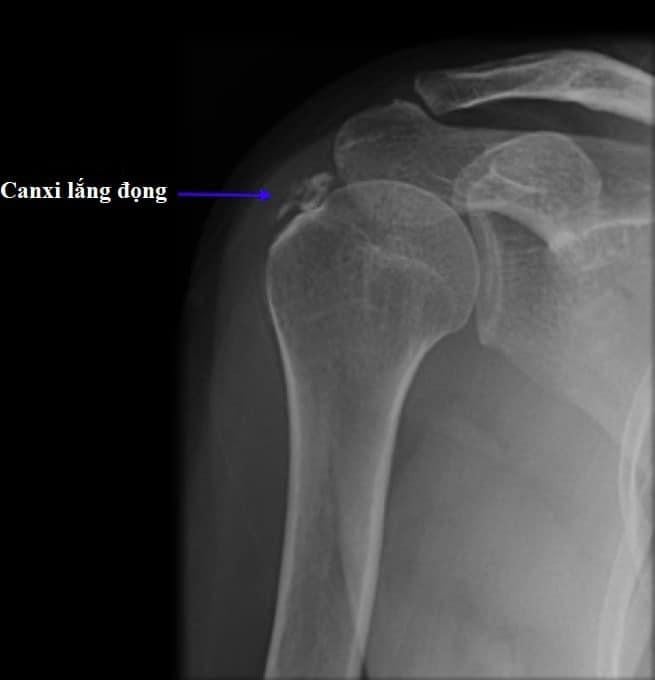

Ngược lại, các tinh thể canxi apatite thỉnh thoảng xuất hiện trong sụn, nhưng thường lắng đọng ở gân cơ, gây ra viêm gân vôi hóa. Bệnh thường xảy ra ở người trẻ và trung niên. Đôi khi, vôi hóa sụn khớp có thể do cả hai tinh thể gây ra.

Tình trạng tích tụ canxi trong gân cơ thường xuất hiện ở các gân cơ chóp xoay ở vai. Bạn có thể bị tình trạng này mà không cần một chấn thương hay hoạt động quá mức gây ra. Những yếu tố quan trọng giúp xác định mức độ nghiêm trọng của viêm gân gồm kích thước, vị trí và số lượng vôi hóa.

Trong chẩn đoán bệnh lý tinh thể canxi, các bệnh lý khác như bệnh gout và nhiễm trùng phải được loại trừ trước tiên. Các xét nghiệm được thực hiện bao gồm lấy mẫu khớp, chụp X-quang và xét nghiệm hóa sinh, xét nghiệm máu. Các thuốc chống viêm không steroid (NSAID) như ibuprofen giúp giảm đau do các cơn cấp tính.